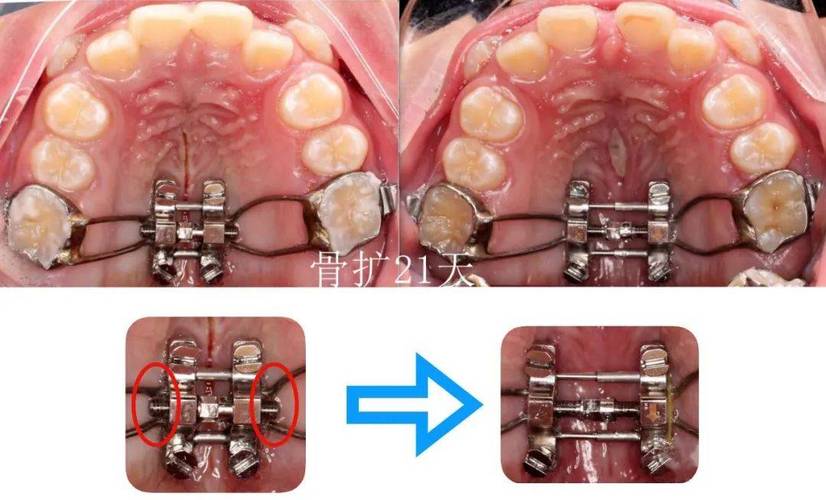

- 片段化:将传统全口弓丝拆分为独立或连接的片段,每个片段对应1-3颗目标牙齿,针对上颌前牙拥挤的片段弓,可能仅包含中切牙、侧切牙的托槽连接段,而磨牙区域保持独立,避免力量传导至非目标区域。

- 精准化:根据牙齿移动需求(如压低、伸长、扭转、内收/外展等),定制弓丝的形态、材质和尺寸,需压低单颗前牙时,片段弓可设计为“L形”,利用杠杆原理将力量集中在牙冠;需纠正扭转时,则通过弯制“转矩”角度,实现牙根的三维控制。

| 复合片段弓 | 结合连续与非连续设计,联合使用辅件(如支抗钉) | 局部牙齿移动与整体咬合调整(如深覆合矫正) | 兼顾局部精准性与整体稳定性,适应复杂病例 |